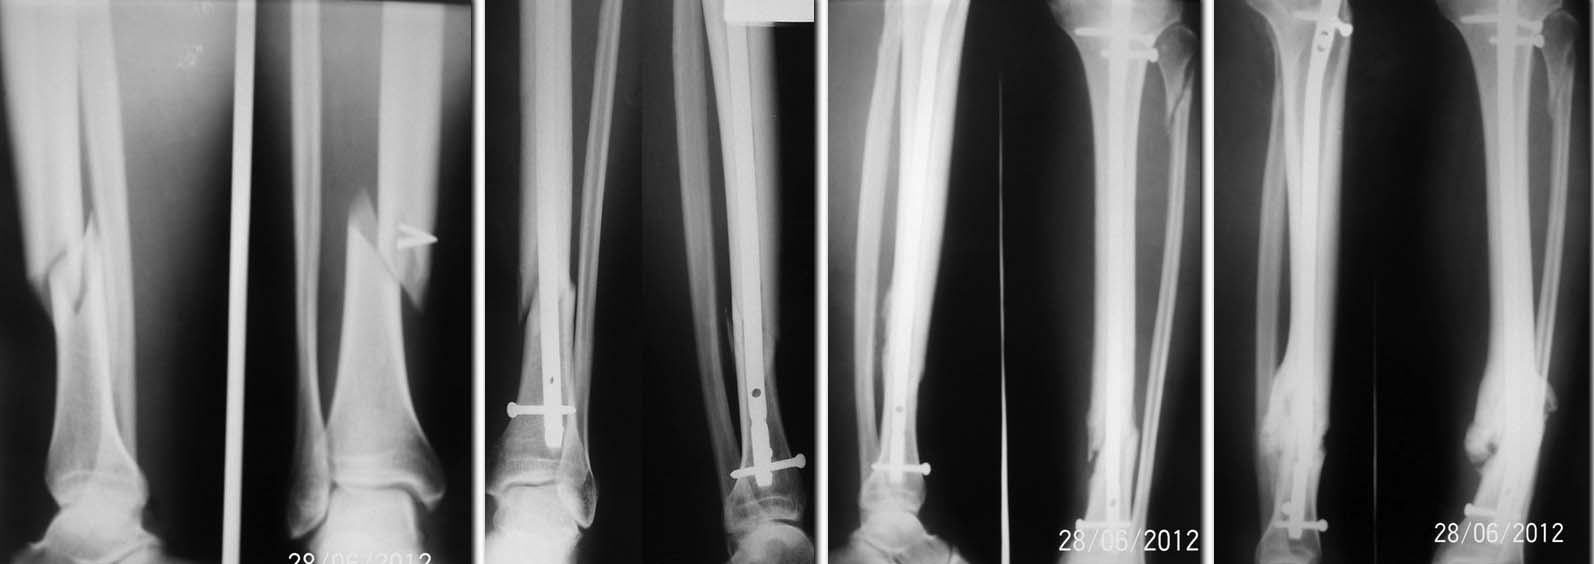

Нам приходилось сталкиваться с подобными случаями, и они заставили нас внести коррективы в интерлокинг инфраистмальных (как впрочем, и супраистмальных) переломов большеберцовой кости. На представленных рентгенограммах – типичный гиперпластический ложный сустав с угловой деформацией отломков. Перелом стержня, можно сказать, «в типичном месте» - через самое проксимальное из дистальных блокирующих отверстий. И ошибки (личное мнение) при выполнении интерлокинга инфраистмального перелома в данном случае тоже типичные. При интерлокинге не учтены особенности именно инфраистмальных переломов. При таких переломах диаметр костномозгового канала дистального отломка уже на уровне перелома всегда больше диаметра стержня. Поэтому исключается плотный контакт стержня и дистального отломка сразу ниже перелома, что намного снижает прочность создаваемого соединения стержень – дистальный отломок. Если нет плотного контакта стержня и кости дистального отломка сразу ниже перелома, то вся ответственность по стабилизации биомеханической системы стержень-дистальный отломок ложится на дистальные блокирующие винты. При инфраистмальных переломах два (даже три) винта не всегда могут обеспечить стабильность создаваемой системы стержень-дистальный отломок, даже если они проведены в разных плоскостях. Это легко можно установить экспериментально. Поэтому мы при интерлокинге инфраистмальных переломов вводим по четыре блокирующих винта, проведенных в разных плоскостях, что обеспечивает гарантию стабильности соединения дистальный отломок-стержень. Также значительно увеличивает стабильность соединения «locking interlocking». Кроме того, в данном случае сыграл свою отрицательную роль при нагрузке и лёгкий варус дистального отломка после интерлокинга. Позволю себе не согласиться с Александром Николаевичем по проблеме ранней динамизации. Сдержанно отношусь к динамизации вообще, как к планируемой рутинной процедуре. В данном случае динамизация ,выполненная в рекомендуемые сроки, никаких проблем бы не решила, поскольку несращение было обусловлено подвижностью в месте перелома дистального отломка из-за нестабильности его соединения со стержнем, а не диастазом или отсутствием компрессии между отломками. Кстати, самодинамизация была (сломанный проксимальный блокирующий винт), но она не предотвратила несращение и перелом стержня, что является лишним подтверждением сказанного выше.

Что касается дальнейшей тактики лечения. Безусловно, обе части сломанного стержня необходимо удалить. Поскольку стержень канюлированный, отломанную дистальную часть стержня можно удалить после удаления проксимальной части через то же отверстие без всяких специальных приспособлений. По-моему, на форуме такой способ уже обсуждался. Пример из личного опыта на фото. Я думаю, принцип извлечения понятен.

Дальше мы бы выполнили остеотомию малоберцовой кости на вершине деформации большеберцовой и после одномоментного устранения угловых деформаций в репозиционном аппарате выполнили бы реостеосинтез блокированным стержнем в режиме статической фиксации. При невозможности одномоментного устранения угловых деформаций в репозиционном аппарате (таких случаев в нашей практике не было) - внеочаговый остеосинтез аппаратом Илизарова с дозированным устранением деформации.